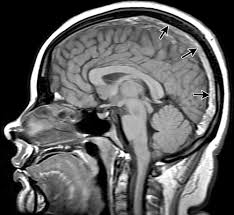

What is this plane view of the brain and why?

Sagittal because you only see one hemisphere, see mid brain, and brain stem